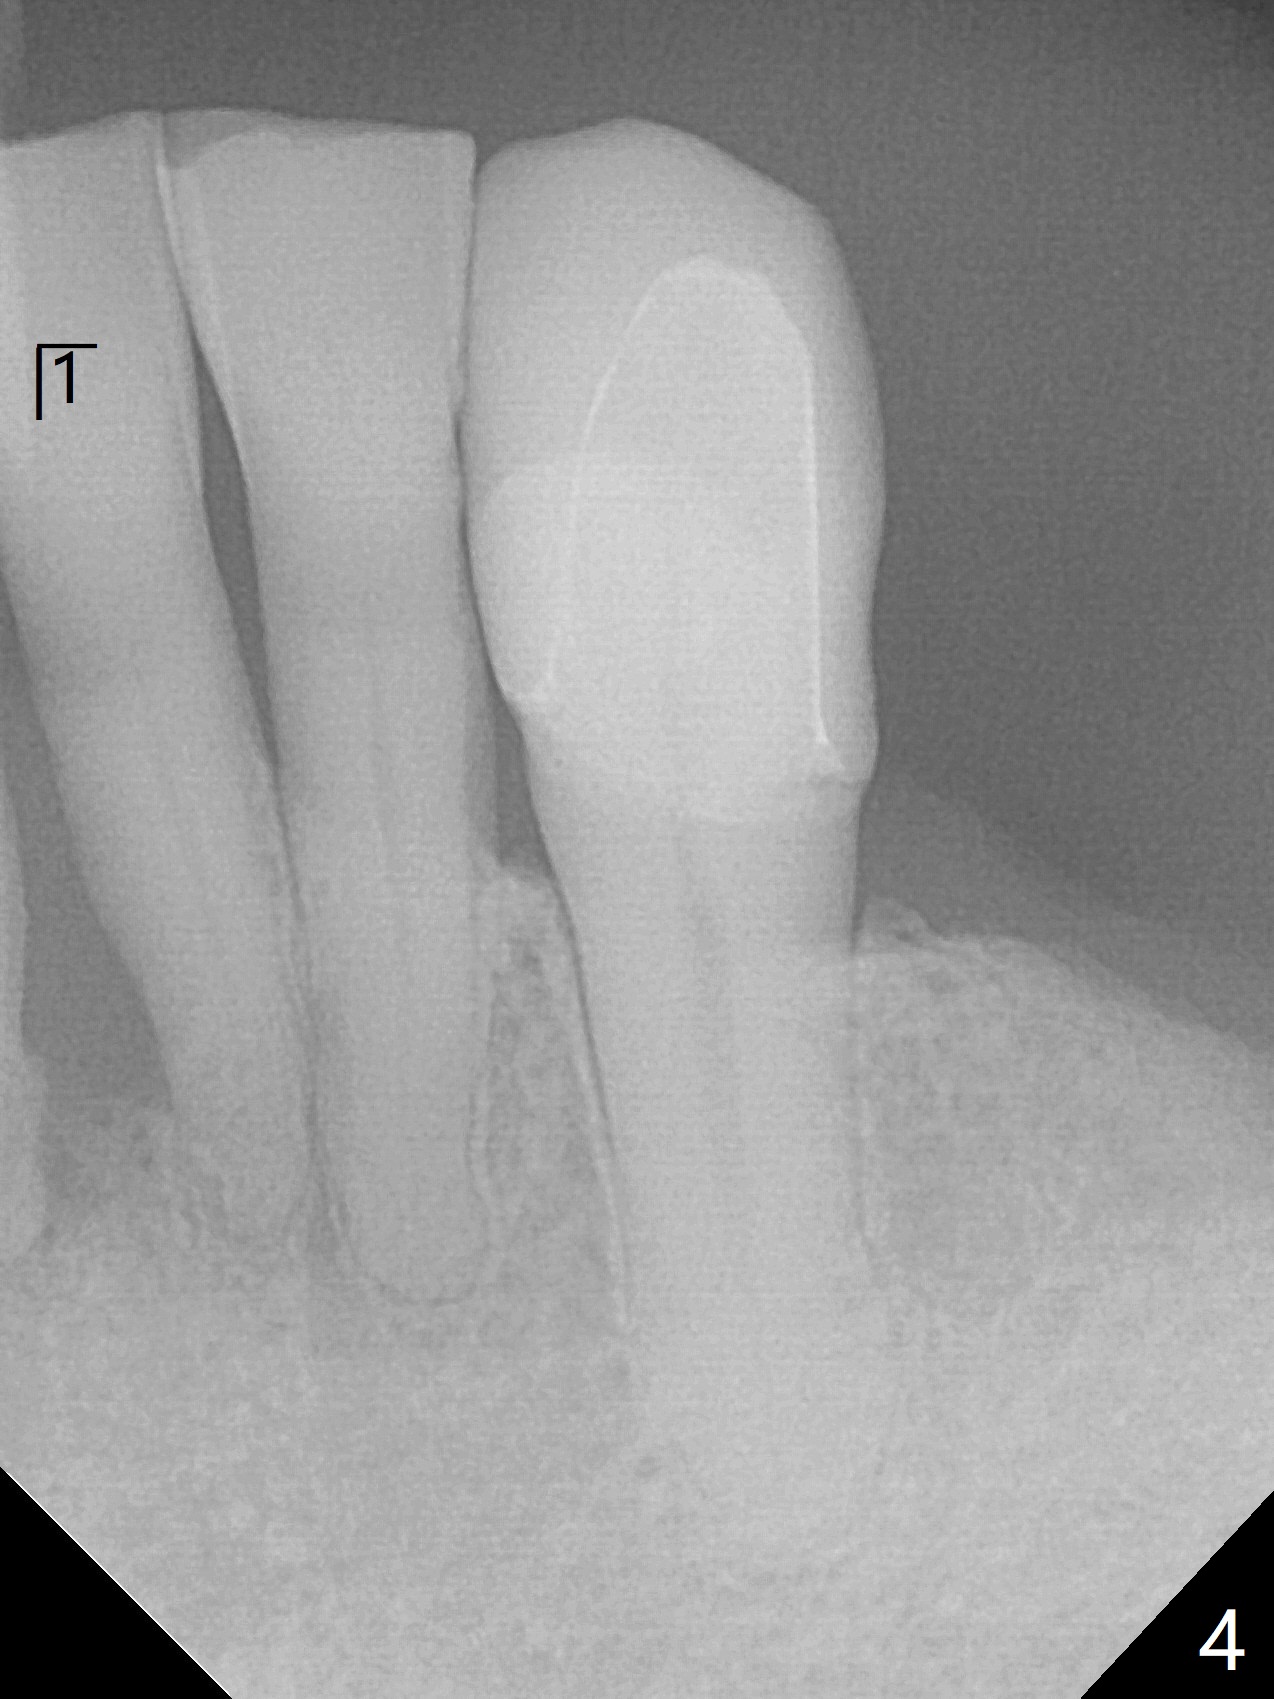

70岁男有上颌全口义齿,下颌局部义齿,后者由于右下切牙肿痛,松动无法戴入(图一至三),左下1骨质吸收严重,但是没有症状(图四)。理想治疗拔除右下1,2,即刻植牙,预防右下三断裂,不过病人没有思想准备,同意即刻植骨(图五,6个月吸收膜)。右下1舌侧,2颊侧脓肿(图一,二),拔牙时发现相应骨质缺损严重。四个月后在右下2植牙,做悬臂桥。当左下1不行时,做单个植牙,这样病人至少可以暂时使用局部托牙。